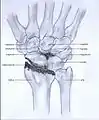

Post-traumatic osteoarthritis can be classified into four stages.[1][6] These stages are similar between SLAC and SNAC wrists. Each stage has a different treatment.

- Stage III: the osteoarthritis is localized in the entire radioscaphoid joint with involvement of the capitolunate joint.

Stage III